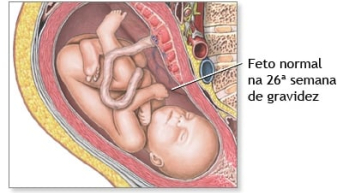

26 semanas

A grande dúvida sempre é: com 26 semanas são quantos meses? Na 26ª semana continuamos no 6º mês de gestação e seu pequeno bebê chegou a um peso de em média 1 kg, implicando que se quadriplicou nas últimas semanas. A partir de agora, seu corpo irá acumular gordura para suportar a temperatura fora da barriga, além de ser fonte de energia nos seus primeiros dias de vida após o parto3.

Devido ao ganho de peso, é natural no sexto mês da gravidez que a mulher comece a sentir dores lombares devido à postura, que se modifica pelo peso da barriga. O aconselhado é ficar o menos possível na mesma posição, devendo se alongar até mesmo para auxiliar na circulação sanguínea, evitando inchaços. Assim termina o segundo trimestre da gravidez.